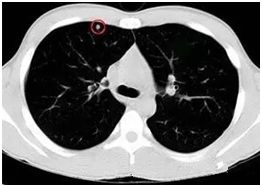

●高危結(jié)節(jié)

●結(jié)節(jié)呈毛栗子樣,周圍有角(棘突)和細(xì)小毛刺生長

●結(jié)節(jié)如月亮,周圍有一圈暈

●結(jié)節(jié)呈分葉狀

●多位于上葉結(jié)節(jié)

●結(jié)節(jié)里有較粗的血管牽扯進(jìn)來

●結(jié)節(jié)里有透亮的小空泡(空氣支氣管征)

●結(jié)節(jié)外圍有胸膜牽拉征象(臍凹征)

●隨訪3—6月以上,結(jié)節(jié)明顯增大或內(nèi)部密度增高

對于以上的高危結(jié)節(jié)應(yīng)由胸外科、腫瘤內(nèi)科、呼吸科和影像醫(yī)學(xué)科醫(yī)生集體會(huì)診,決定是否需要進(jìn)一步檢查(包括支氣管鏡、CT增強(qiáng)掃描、經(jīng)皮穿刺活檢等)明確診斷,以及采取什么方法治療。

對高度懷疑為惡性者且適合于外科手術(shù)者,首選手術(shù)治療。對肺癌可能性小的病例可抗炎治療7—10天,休息一周后復(fù)查,結(jié)節(jié)增大或無變化,可進(jìn)入臨床治療,結(jié)節(jié)縮小可動(dòng)態(tài)隨訪。